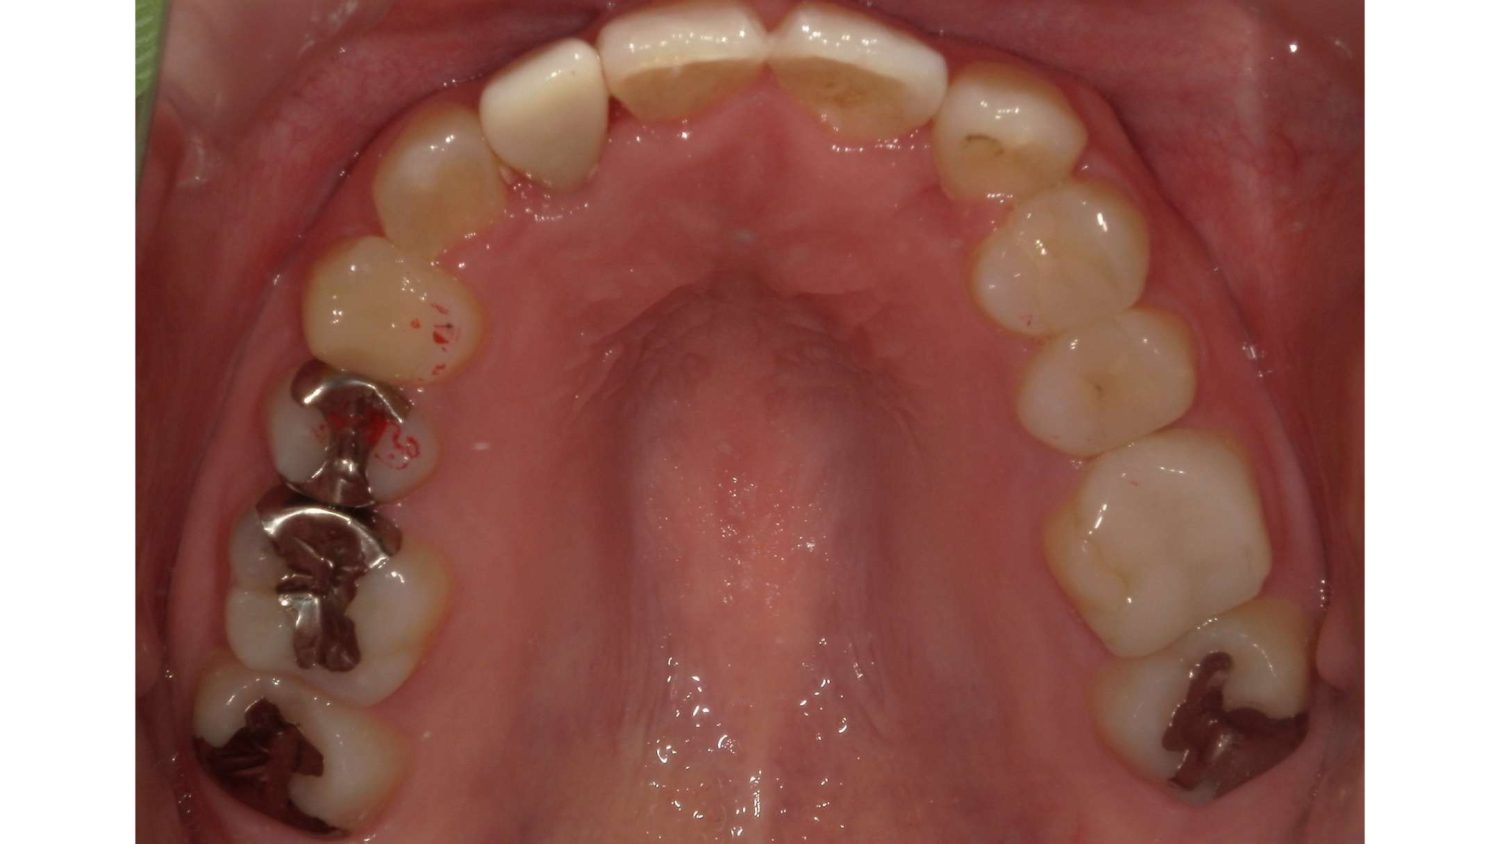

前歯だけの矯正の症例紹介③

Before

After

主訴

前歯の歯並びを改善したい。

治療内容

後ろに引っ込んでいる左上側切歯は抜歯し、ワイヤー矯正で治療しました。

治療費

115,500円(税込)(リテーナー込み)

治療期間

3か月

通院回数

5回

想定されたリスク

※左右対称にならない

石毛 俊作先生

大神宮デンタルクリニック

左上側切歯を抜歯したほうが見た目は左右対称に見えやすかったが、左上犬歯を抜歯すると側切歯を動かす距離が多くなってしまい治療期間が長引くのと歯根にダメージを与える可能性があったため、患者様と相談し、側切歯のほうを抜歯しました。